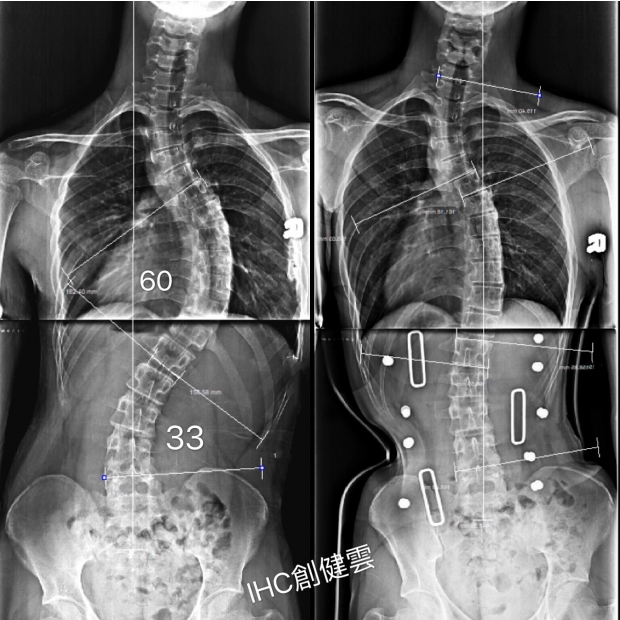

15歲S型極重度側彎男孩

胸彎60度,腰彎33度